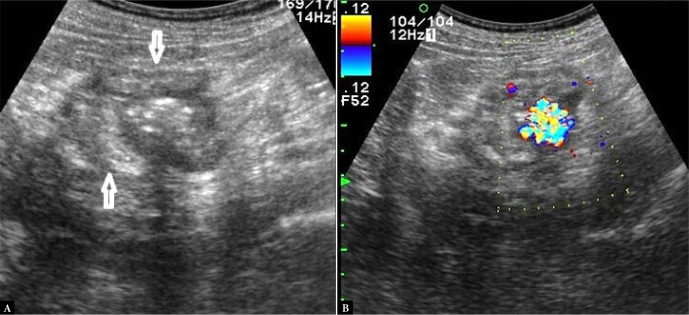

The aim of this paper is to present our experience in transabdominal ultrasonography of ileocecal valve lesions. The ileocecal valve, located in the central part of the ileocecal bowel segment, is rarely the primary site of disease processes. It is usually involved by pathologies in adjacent bowel segments. These are primarily infectious diseases such as yersiniosis, campylobacteriosis and salmonellosis. Typical location of Crohn's lesions also promotes valve involvement. The appearance of the lesions in these cases is characterized by a symmetrical submucosal thickening of the bowel involved over a longer segment. Non-malignant valvular hyperplasia is relatively commonly identified as lipomatosis, manifested by symmetrical enlargement and smooth outlines. However, valvular lipoma causing an asymmetrical hyperechoic bulge is a rare finding. ileocecal valve lipomatosis or lipoma should not be misdiagnosed as a lipoma of the cecoascending part of the colon and, the other way round, a right colonic lipoma should not be mistaken for a fatty valve. Polyps on the ileocecal valve, although sometimes detected, were not identified in our material. Adenocarcinoma, which is found in the cecum in approximately ¼ of cases, is the most common malignancy, followed by neuroendocrine tumor and, rarely, lymphoma. In three cases of malignant involvement of the ileocecal valve, we observed irregular hypoechoic thickening with complete loss of wall stratification, with the lesions causing symptoms of small bowel obstruction in two of these cases. The nearly forgotten ileocecal valve syndrome, also known as Bauhin's ileocecal valve syndrome, characterized by intermittent right iliac fossa pain, is also briefly discussed. Transabdominal ultrasound can be used as an initial diagnostic tool in some of these pathologies.

Abstract Image